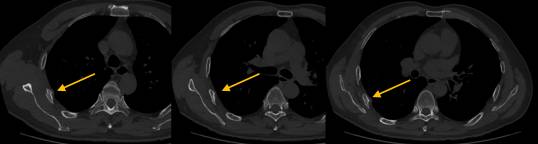

患者,男,56岁,胸部CT示右侧第4-6肋骨骨折,这本是十分正常的事情,但当我看了患者的前片后怀疑这两次检查不是同一个患者,因为第一次CT检查患者未见明确骨折(图1),第二次检查右侧肋骨可以看到明显的骨折线,部分断端错位,邻近胸膜肿胀(图2箭头所示)。

图1

图2